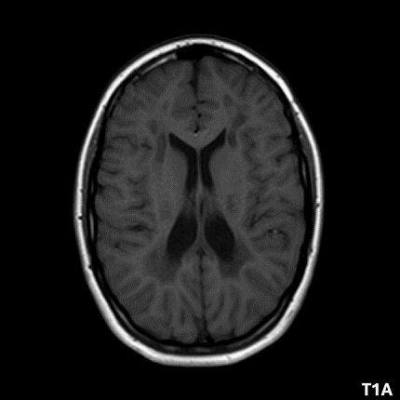

- A) Aksiyel T2A ve koronal T2A sekanslarda sentrum semiovale, korona radiata ve bazal ganglionlar düzeyinde bilateral frontoparietal derin periventriküler beyaz cevherde birleşme eğilimi gösteren hiperintens gliotik sinyal değişiklikleri (oklar) ve aksiyel T2A serilerde servikal spinal kordda posterior kolonda, lateral kesimlerde sinyal artımları (oklar) izlendi.

- B) Kontrastsız T1A serilerde tarifli alanlarda hipointens (oklar) görünüm izlendi. Kontrastlı T1A serilerde bu düzeyde (oklar) kontrastlanma artışı izlenmedi. Diffüzyon ağırlıklı serilerde belirgin diffüzyon kısıtlaması (oklar) görülmedi.

- LBSL, karakteristik radyolojik özelliklere sahiptir. MRG’de tipik olarak bilateral ve simetrik beyaz cevher sinyal değişiklikleri görülürken, subkortikal U lifleri, internal kapsülün posterior kolları, trigeminal sinir traktları, serebellum, korpus kallozumun spleniumu, medulla oblongata ve omurilikteki dorsal kolonlar ile lateral kortikospinal traktlar genellikle korunur.

- Etkilenen bölgelerde T1’de hipointens, T2/FLAIR’da hiperintens sinyal değişiklikleri izlenir. DWI’de lezyonların periferinde kısıtlı difüzyon görülebilir. MRS’de beyaz cevherde laktat artışı saptanabilir, ancak bu her hastada mevcut değildir.

- LBSL tanısında majör kriterler; subkortikal U lifleri korunmuş serebral beyaz cevher, servikal düzey dahil omurilik dorsal kolonları ve lateral kortikospinal traktlar, medulla oblongata piramitleri veya medial lemniskus dekusasyonu tutulumu iken; minör kriterler korpus kallozum spleniumu, internal kapsül posterior kolu, superior ve inferior serebellar pedinküller, trigeminal sinir traktları, mezensefalik trigeminal yollar, medulla oblongata anterior spinosebellar traktları ve serebellar beyaz cevherdeki sinyal değişiklikleridir.